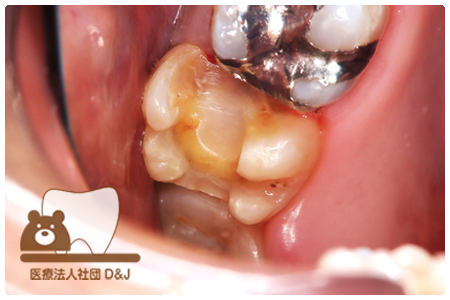

症例3フリジルコニアクラウン 左上6

治療前

治療後

59歳 男性

- 治療内容

- 虫歯で大きく失われた歯に対して、土台としてファイバーコアを使用し、その上にフルジルコニア製の被せ物を装着しました。見た目と強度を両立した自由診療の治療です。

- 治療期間

- 根の治療含めて3カ月半

- 費用

- 自費

フリジルコニアクラウン:77,000円(税込)

(R8.2月時点)

- その他の治療の費用は含まれておりません。

- リスク・副作用

- 強い力が加わると割れる可能性があります。また、噛み合わせや歯ぎしりの影響で脱離することがあります。